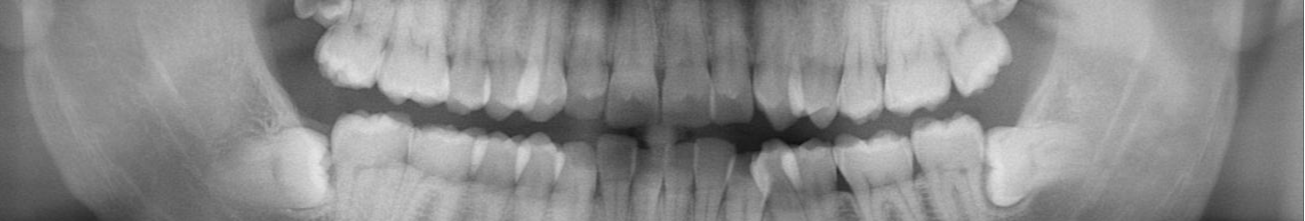

clear agliner progect

great work very fast . ortho treatment planning